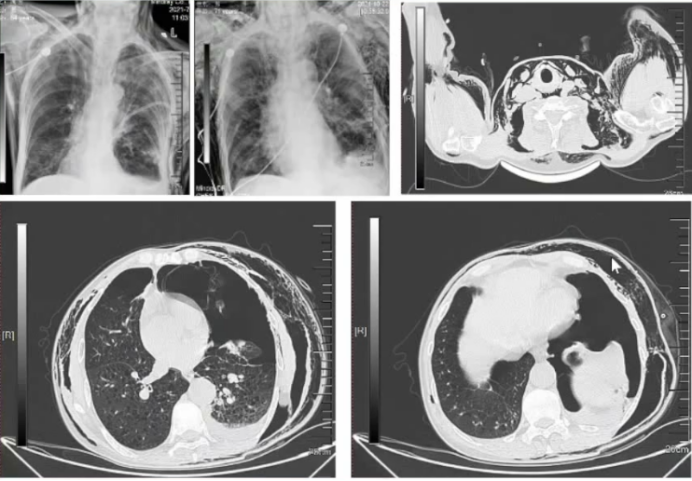

1)皮下气肿:“Double-Trocar”内科胸腔镜下肺大疱减容术目前最棘手的并发症是皮下气肿,严重者可能会压迫气管(图4)。所以部分患者术后可能会出现呼吸困难加重。既往对于这部分患者尚无良好的治疗方式,本团队积极探索,目前通过迷路置入胸腔闭式引流管,有效地改善了术后皮下气肿的发生,但该方法仍需进一步验证。

图片

4  “Double-Trocar”内科胸腔镜下肺大疱减容术后皮下气肿并发症